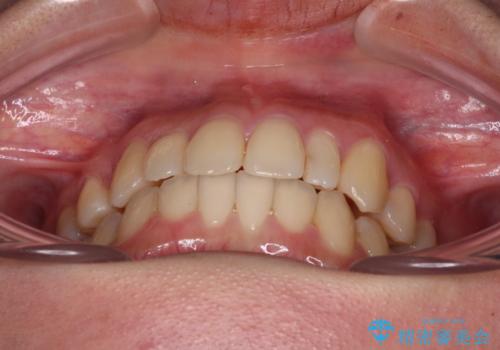

八重歯の抜歯矯正 補助装置を用いたインビザライン矯正

- 上顎の重なっている前歯を気にして来院された患者様です。

重なっている部分は抜歯が必要で、歯の移動量が多く、更には右側にずれている正中を改善する必要がありました。

インビザライン単体での治療は困難と判断し、補助装置により八重歯移動後にインビザラインを用いることとしました。

非常にしっかりとマウスピースを装着してくださいましたが、前歯の排列がなかなか仕上がらずに期間がかかってしまいました。